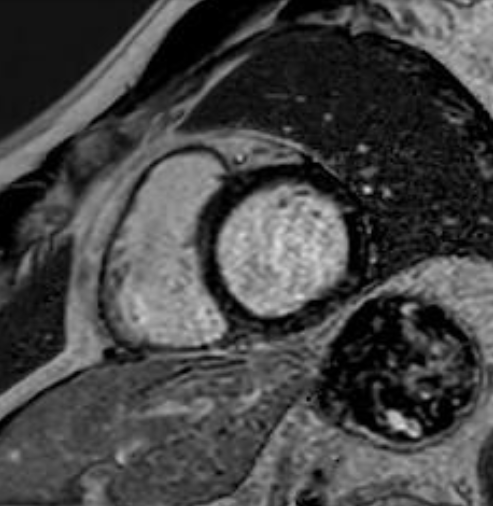

T1 mapping in the hypoperfused region demonstrating reduced native T1 values.

First-pass gadolinium imaging demonstrating a perfusion defect in the inferolateral wall..png)